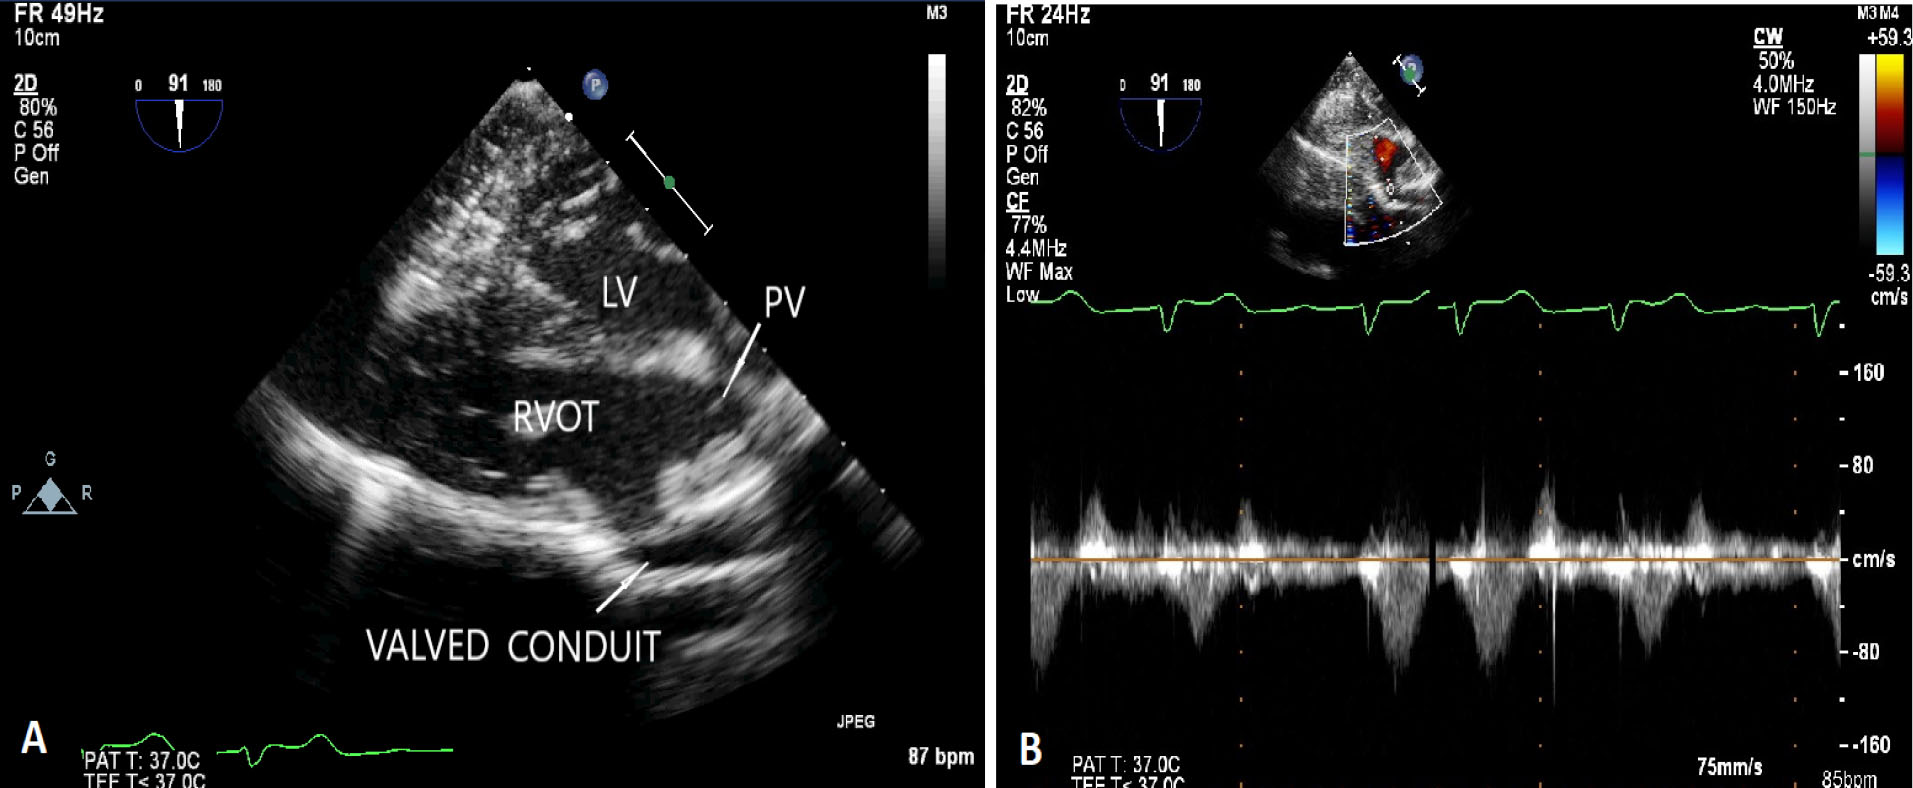

jcvtr-13-87-g003

Figure 3. (A) Postoperative transesophageal echocardiography showing native unicuspid pulmonary valve and valved conduit. LV - left ventricle, PV - native unicuspid pulmonary valve, RVOT - right ventricular outflow tract (B) Postoperative transesophageal echocardiography with pulse wave doppler across the valved pericardial autologous conduit showing minimal gradient of 8 mm Hg

A 11-year-old girl, weighing 21 kg presented with the complaints of dyspnea and cyanosis while playing with room air oxygen saturation of 75-85%. The diagnosis of TOF was confirmed by transesophageal echocardiography and cardiac catheterization study. The cardiac catheterization study showed single coronary artery arising from right aortic sinus with anomalous course of left circumflex artery crossing the RVOT (/Supplementary Video S1). There was absence of the intrapericardial and hilar segments of left pulmonary artery (). Multiple small aortopulmonary collaterals were seen separately supplying the left lung without reformation of the hilar branch pulmonary artery. The right pulmonary artery (Nakata Index Z score +2) and left ventricle (left ventricular end diastolic volume index > 30 ml/m2) were normal sized (). Patient was planned for primary single lung intracardiac repair. Intraoperatively, a single coronary artery was arising from right aortic sinus which was immediately dividing into right coronary artery, left anterior descending artery and left circumflex artery (). The right coronary artery had normal course. The left anterior descending artery was crossing RVOT far off from the pulmonary annulus. The left circumflex artery was crossing RVOT, very close to the pulmonary annulus (). Pulmonary annulus was hypoplastic with poststenotic dilatation of main pulmonary artery. The main pulmonary artery was continuing as right pulmonary artery with completely absent left pulmonary artery. The left lung was small and fibrotic with multiple small collaterals seen around the hilum without hilar reformation of the branch pulmonary artery. The handmade valved pericardial autologous conduit (12 mm diameter) with bicuspid pulmonary valve reconstruction using polytetrafluoroethylene membrane was prepared by the technique described by Schlichter et al. 4 The ventricular septal defect was closed using autologous glutaraldehyde treated pericardium. The hypertrophied infundibular muscle was excised. The native pulmonary valve was unicuspid and hypoplastic. Leaflet tethering was released. Hegar’s dilator of 7 mm size was negotiated through the hypoplastic pulmonary annulus. The valved pericardial autologus conduit was then anastomosed, first at the pulmonary end followed by the ventriculotomy end (). The post-operative right ventricular systolic pressure was 50% of systemic systolic pressure. The transesophageal echocardiography showed gradient of 8 mm Hg across the valved conduit and mild neopulmonary valve regurgitation (). The patient recovered uneventfully. The patient was discharged on 11th post-operative day and is doing well in the follow-up period.